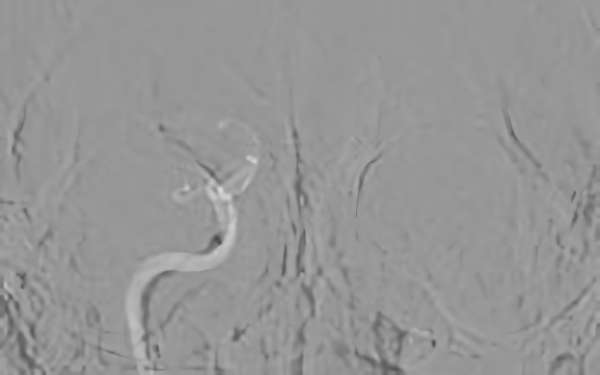

症例 '20年3月

No.

786

'20年3月19日

塞栓性脳梗塞

60代

兵庫県の病院

手術写真

治療

前

中

後

手術日